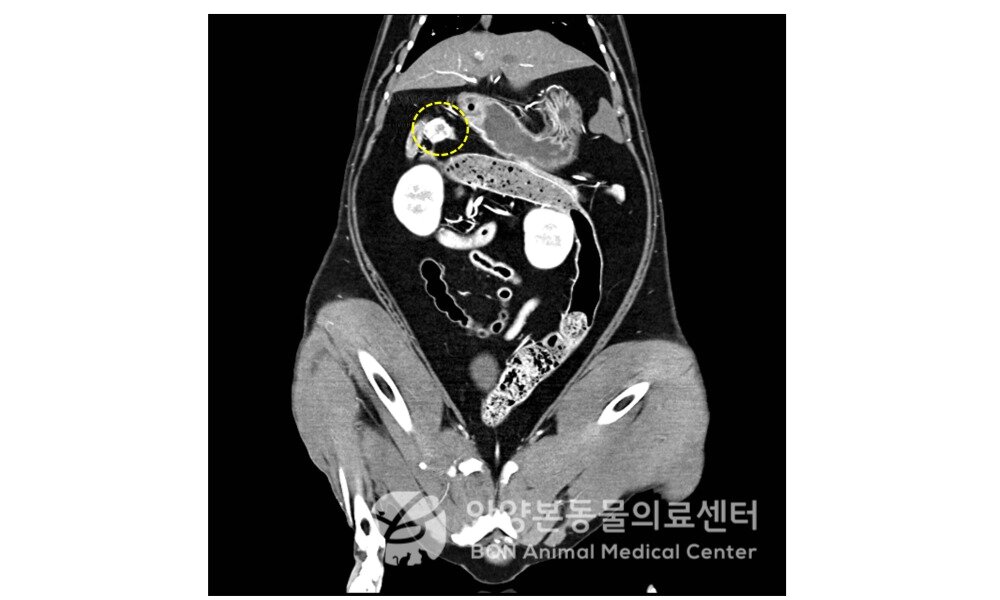

본문 이미지 - 인슐린종이 진단된 고양이의 CT 영상(본동물의료센터 제공) ⓒ 뉴스1

인슐린종이 진단된 고양이의 CT 영상(본동물의료센터 제공) ⓒ 뉴스1